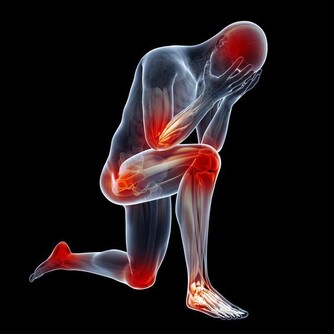

30歲開始,關節痠、痛、軟!

你知道嗎,我們的關節每天所承受的壓力有多重?

其實除了平躺的時候,其他時候膝蓋一直都在負重。

有研究指出,

走路時膝蓋所承受的重量,是體重的1~2倍;

上樓梯則多增加1倍,變成3倍;

跑步時,更要承受4倍的重量,實在令人難以想像!